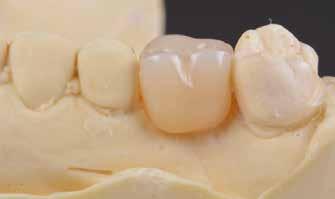

Protetikai eljárás

A teljesen digitalizált protetikai munkafolyamat során az Exocad szoftver segítségével (exocad) egy hibrid, csavarrögzített, cirkónium monolit koronát gyártottunk le copaSKY

uni.fit titánalapra (bredent medical). Az implantátum körül a bukkális lágyszövet megfelelő vastagságot és kedvező ínykontúrt mutatott (12. a–b. ábra). Az egyedi ínyformázó eltávolítása után egészséges implantátum körüli lágyrészgallér

volt megfigyelhető (13–14. ábra), ezen kívül közvetlenül a műtét előtt intraorális vizsgálatot végeztünk a lágyszöveti profil megállapítása érdekében. Ezt követte a scanbody behelyezése, így digitális lenyomat készült az implantátum pozíciójáról (15. ábra). Ugyanezzel a technikával rögzítettük az antagonista fogívet és a harapást is. Az így kapott STL-fájlokat digitálisan továbbítottuk a fogtechnikai laboratóriumba. A titánalapra PMMA ideiglenes koronát készítettünk a proximális és marginális illeszkedés ellenőrzése érdekében, valamint a megfelelő harapás elérése céljából (16–17. ábra) Miután az összes igazítás elkészült, ismételt vizsgálatot végeztünk. A végleges hibrid csavarrögzítésű, teljes kontúrú cirkóniumkoronát titánalapon erősen polírozott szubgingivális résszel készítettük el, és 25 Ncm nyomatékra húztuk (18. ábra). Kiváló árnyalategyezést és klinikai eredményt

18. ábra: Végleges, hibrid, csavaros rögzítésű, monolit cirkóniumkorona titánalapon, fényezett ínygallérral.

használatát, és jobb kommunikációt tesznek lehetővé a fogtechnikai laborral [10]. Ebben az esetben egy hibrid csavarrögzített pótlást terveztünk és kiviteleztünk. Egy átfogó áttekintés, amely a csavarozható és ragasztott koronák klinikai jelentőségére összpontosított a döntéshozatalban, azt állapította meg, hogy a csavaros rögzítésű pótlás kevesebb biológiai szövődményt mutat, illetve előnye, hogy könnyen javítható anélkül, hogy károsítaná az ínyformázót és a koronát [11]. A cementtel rögzített korona eltávolítása még mindig nagyobb kihívást jelent és kevésbé kiszámítható, mint egy csavaros pótlásé [11]. Így a csavarozható pótlás leegyszerűsíti a kezelést, amennyiben a jövőben bármilyen komplikáció lépne fel. A cement kifolyása és az implantátum körüli mucosa alatt maradása mikrobiális kolonizációt és az implantátum körüli szövetek károsodását eredményezheti. A csavarrögzített pótlásokkal könnyebben megoldható a szájhigiénia, és egyszerűbben elvégezhetők a fenntartó kezelé-

sek [12]. A végleges pótláshoz polírozott, teljes kontúrú (full contour) cirkóniumkoronát használtunk. A réteges cirkóniumkoronákban a leplezőkerámia hosszan tartó kopás után berepedezést vagy akár leválást mutat, ami a helyreállítás meghibásodását eredményezi [13]. A monolit koronák CAD/ CAM technológiával készülnek, nagy a hajlítószilárdságuk és törésállóságuk, nagyobb, mint az alumínium-oxid alapú kerámiakoronáké [14].